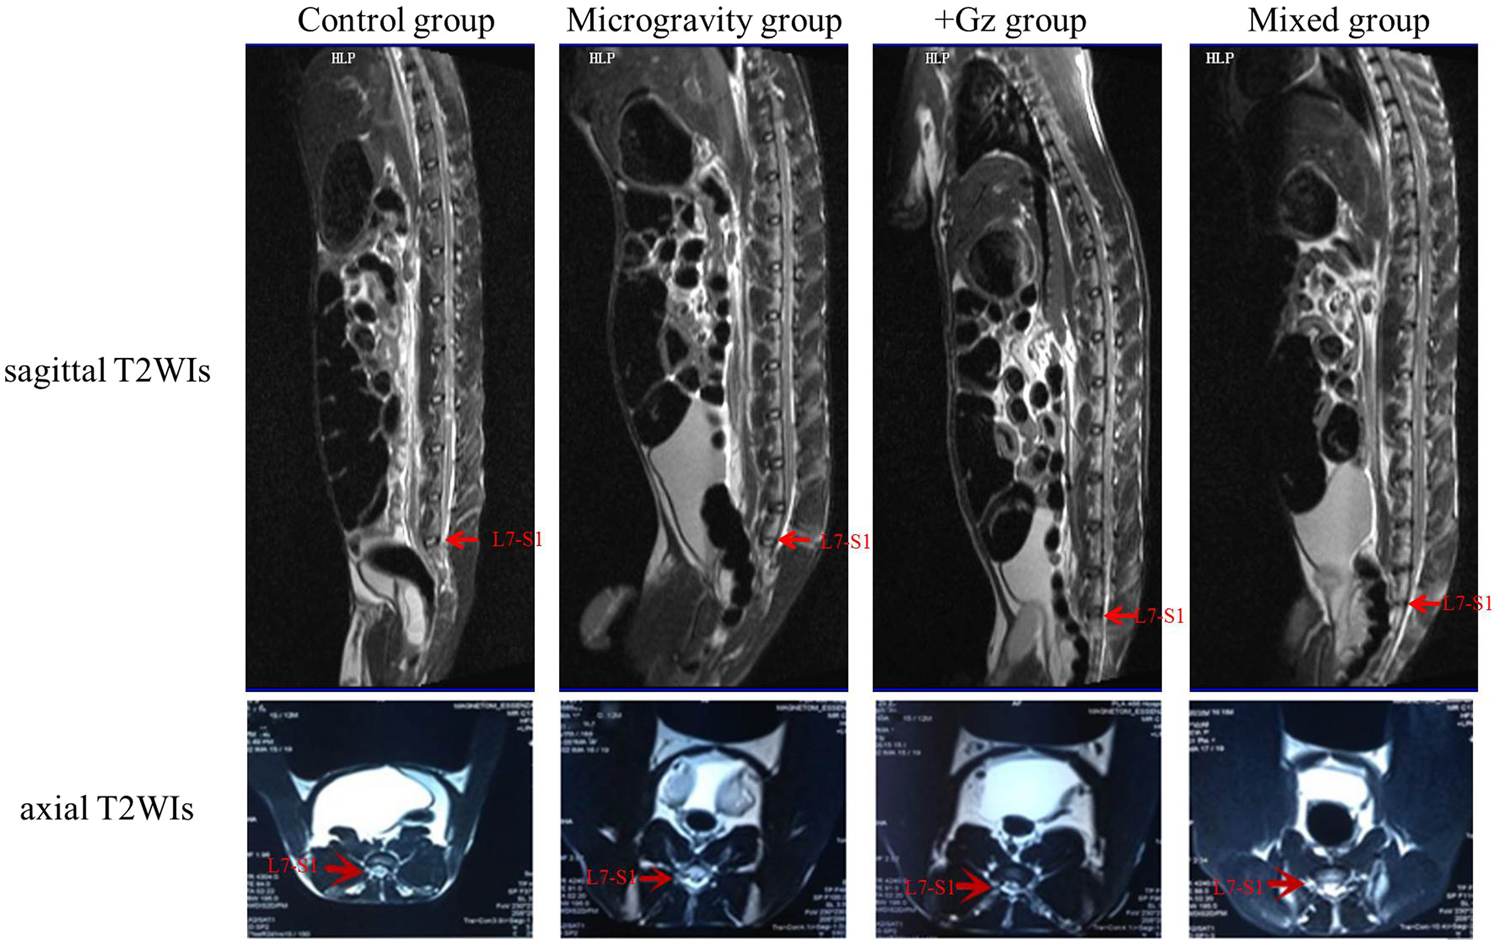

Figure 2

Imageological results of animals in each group. As shown by the sagittal T2WIs at 24 weeks, the IVD at L7–S1 of one animal in the control group was classified as Pfirrmann grade I (red arrow). The structure of the disc is homogeneous with a bright hyperintense white signal intensity and a normal disc height. Similarly, the IVD at L7–S1 of one animal in the microgravity group was classified as grade II (red arrow). The structure of the disc is inhomogeneous with a hyperintense white signal. The distinction between the NP and AF is clear, and the disc height is normal, with or without horizontal gray bands. Grade III (red arrow) in the +Gz group: The structure of the disc is inhomogeneous with an intermediate gray signal intensity. The distinction between the NP and AF is unclear, and the disc height is normal or slightly decreased. Grade IV (red arrow) in the mixed group: The structure of the disc is inhomogeneous, with a hypointense dark gray signal intensity. The distinction between the NP and AF is lost, and the disc height is normal or moderately decreased. As shown by the axial T2WIs, spinal stenosis developed in all of the experimental groups, but not the control group.